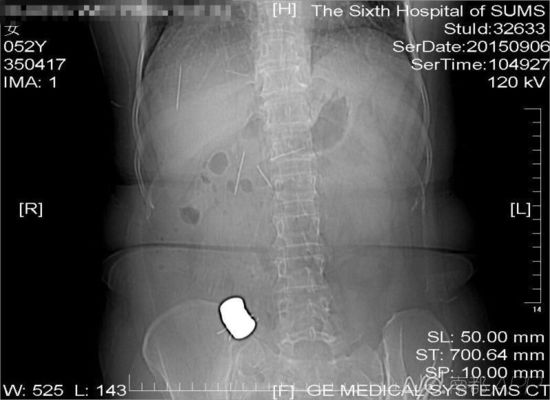

CT檢查結果中顯示,老人腹中有多個金屬異物和散落的繡花針

進行的CT檢查結果顯示,黃姨腹中有多個金屬異物和散落的繡花針。主管醫生黃俊博士介紹,這些針分別位于黃姨小腸內,部分已經穿出小腸散播于腹腔內,還有部分金屬異物,最大的一塊上附著了數根斷針,有一根插進了胰腺,剩下的一根在脊柱附近,每枚約長4厘米。